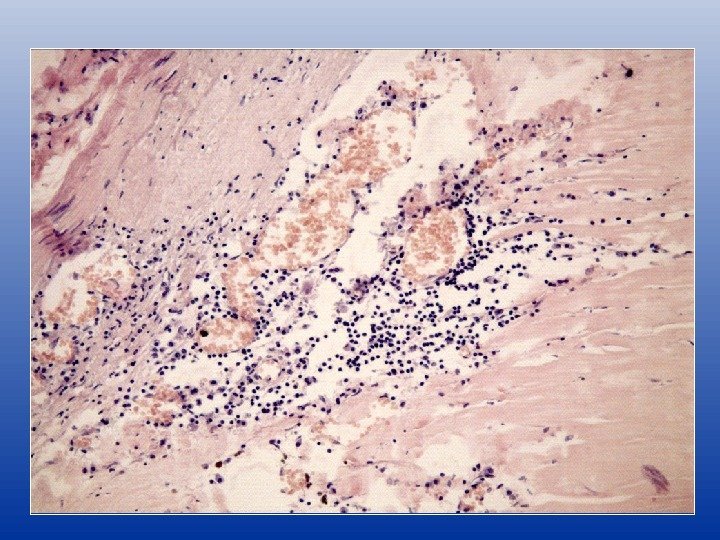

Неоангиогенез и воспалительная реакция

Воспалительная реакция в различных слоях артериальной стенки